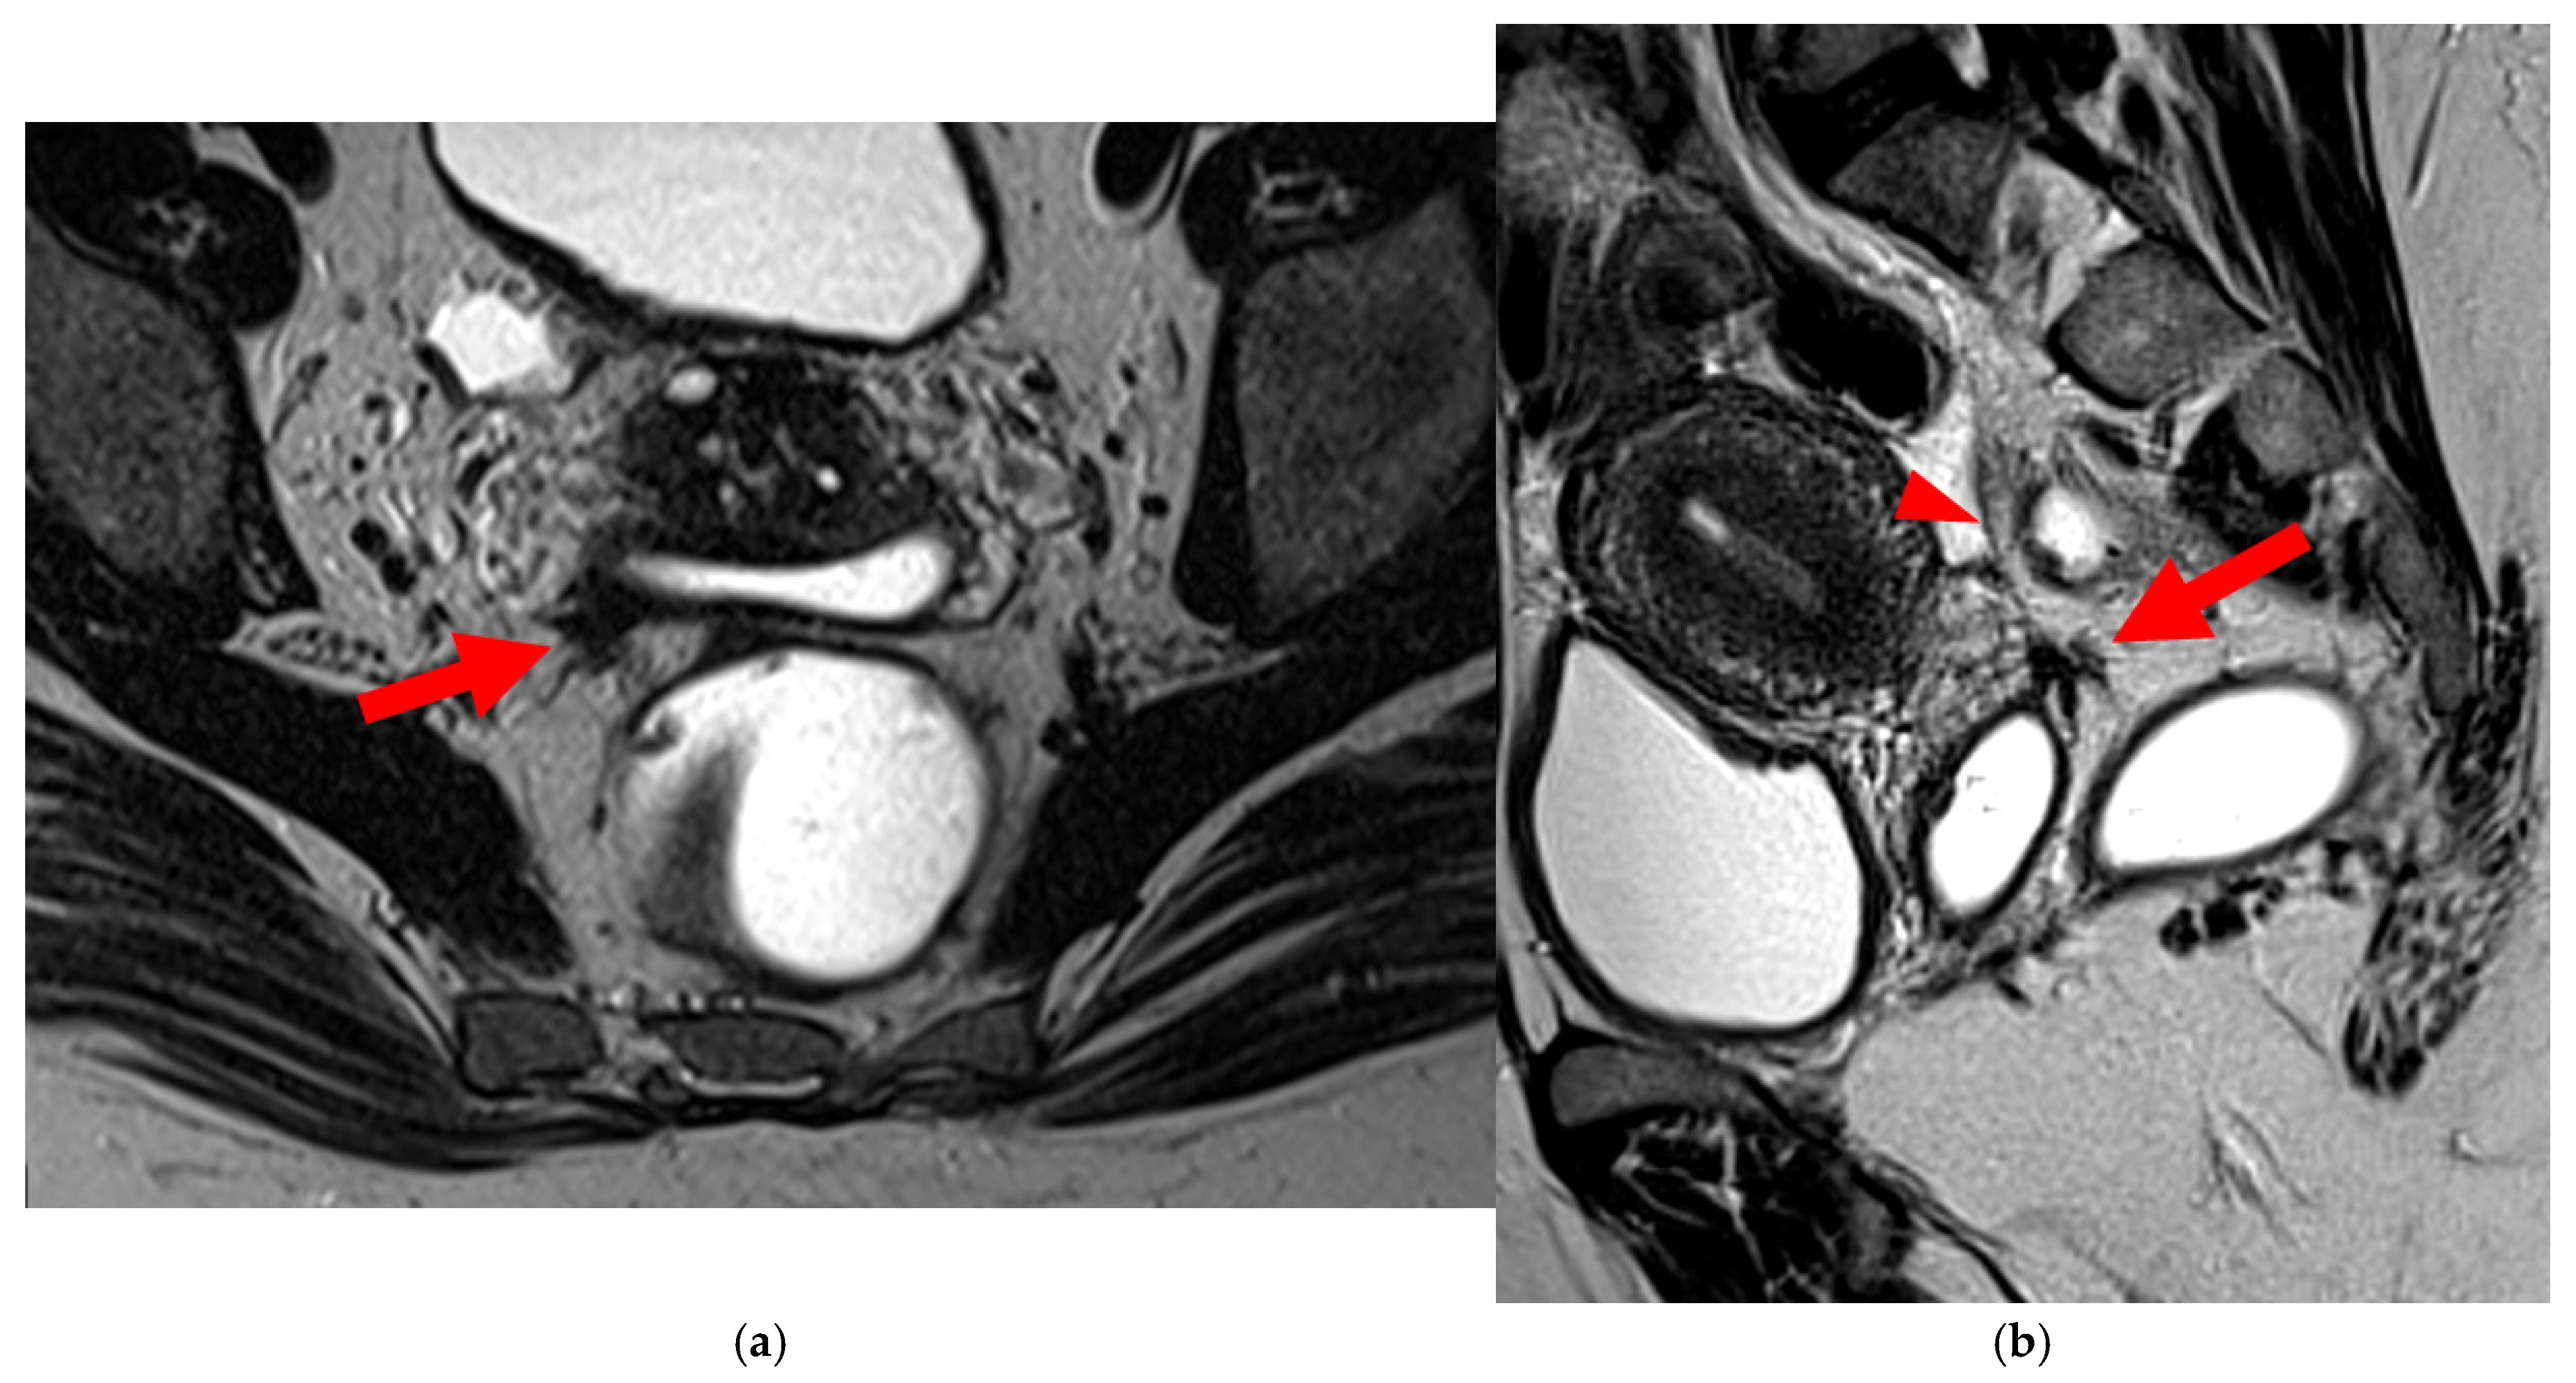

Figure 14. Pelvic MRI scan of a patient with a HTD type 6 USL. (a) Axial T2WI shows a visible but thin (1.6 mm) left USL (dashed arrow) and a thick (3.5 mm) but smooth right USL (arrowhead), initially classified as a type 2 left USL and a type 3A right USL. (b) Axial fat-suppressed T1WI reveals hyperintense hemorrhagic spots within the left sciatic nerve (arrow). (c) Axial T2WI demonstrates spiculated nodularity within the left sciatic nerve (arrow), leading to reclassification as type 6 left USL due to this so-called “visceral” nerve involvement. Note the neurogenic amyotrophy (red star) of the left piriformis and gluteal muscles, including the gluteus maximus, gluteus medius, and gluteus minimus.

A type 6 USL is associated with adjacent pelvic “visceral” involvement in a broad sense. It most commonly affects the digestive tract (Figure 8 and Figure 9), with the rectum and rectosigmoid junction wall thickening: in this case, the lesion often appears as a “medallion-shaped” protrusion into the lumen. Less frequently, the urinary tract is affected (Figure 9 and Figure 10), involving the muscular layer of the bladder or even the distal ureter at the level of the common iliac artery, with stenosis potentially leading to upstream hydronephrosis. More rarely, as USLs are also close to nearby pelvic nerve structures (Figure 11), contiguous involvement of the inferior hypogastric plexus located in the sacro-recto-genital septum (a.k.a. Delbet sagittal fascia) beneath the distal two-thirds of the USL, or exceptional involvement of the sciatic nerve adjacent to the pelvic wall, is possible (Figure 12, Figure 13 and Figure 14).